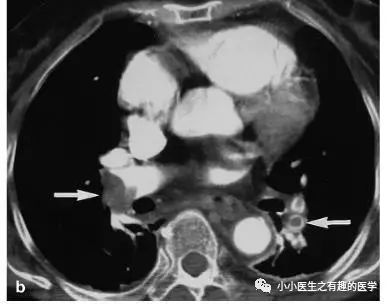

上面的患者,增强CT放大了。

下面是另外一个